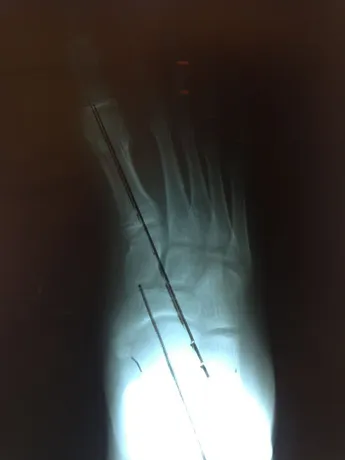

Pre and Postop X-rays Subtalar Joint Implant (Below)

Patient JD